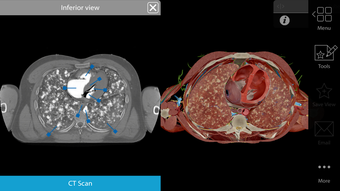

One of the most remarkable features of this application is that it enables users to compare 3D models of normal anatomy with models of common diseases and conditions. Furthermore, users can set the heart rate and visualize conduction in a dissectable, beating 3D heart while following along on an ECG. The application also presents animations that demonstrate the physiological processes of gas exchange, pulmonary ventilation, fluid balance, peristalsis, and more. Interactive lessons walk users through the progression of atherosclerosis, kidney stones, lung cancer, and other common conditions, and quizzes test users' knowledge of various physiological processes and pathologies.